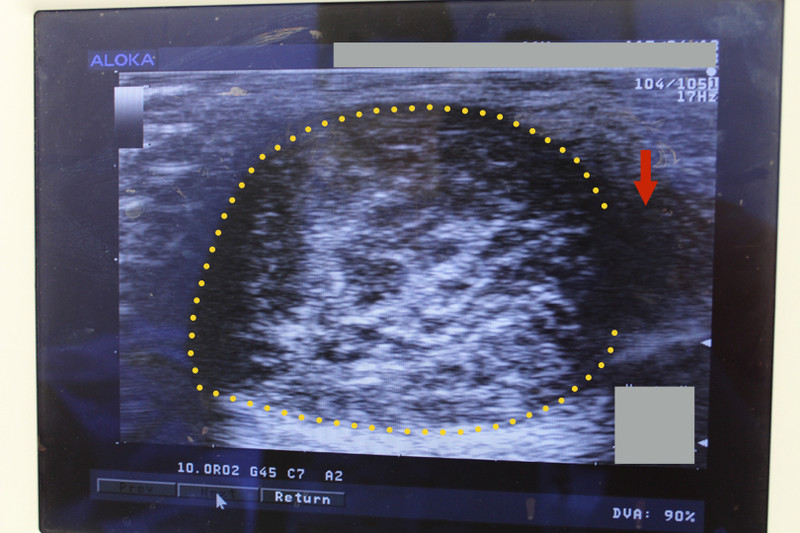

今回の症例も頚部の粉瘤腫で、くりぬき法を行います。

消毒&局所麻酔後に、いつものように4mmトレパンで穴をあけます。

腫瘍の袋も絞り出されました。できるだけまわりの組織に触れないように袋を取り出します。慎重に!

最後は縫合して軟膏をぬって終了です。縫わなくてもいいんですが、今回も縫った方がきれいになりそうで縫いました。腕の麻痺が無いかチェックすることも大切です。でも、結局15分程度で終わっちゃいました![]()